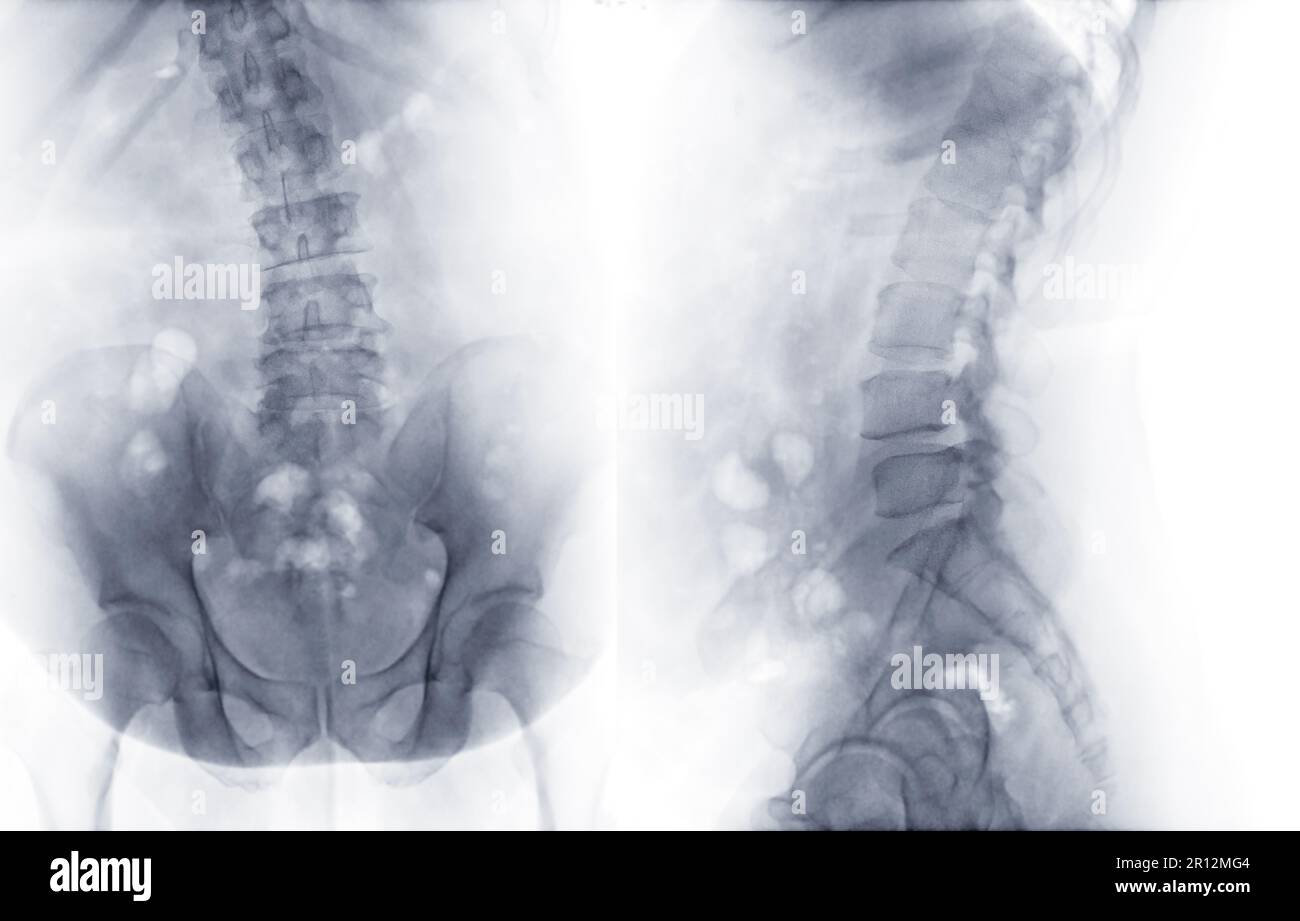

Preoperative AP and lateral plain radiographs of the lumbar spine

Anteroposterior (AP; a) and lateral (b) radiographs of the lumbar spine What Is Lumbar Spine Ap And Lat Lumbar spine ap or pa. Injured patients should not be turned over. Purpose and structures shown a basic view of the lumbar spine. The lumbar spine lateral view images the lumbar spine which generally consists of five vertebrae (see: In the lateral decubitus position, position the patient so that the humeri are extended 90 degrees to the thorax, with the. What Is Lumbar Spine Ap And Lat.

Xray image of lumbar Spine or Ls spine AP and lateral view for What Is Lumbar Spine Ap And Lat Lumbar spine ap or pa. In the lateral decubitus position, position the patient so that the humeri are extended 90 degrees to the thorax, with the elbows flexed so that the forearms are parallel. Correct alignment of cr and l5 to s1 is evidenced by an open joint space. Position of patient supine or prone. The lumbar spine lateral view. What Is Lumbar Spine Ap And Lat.